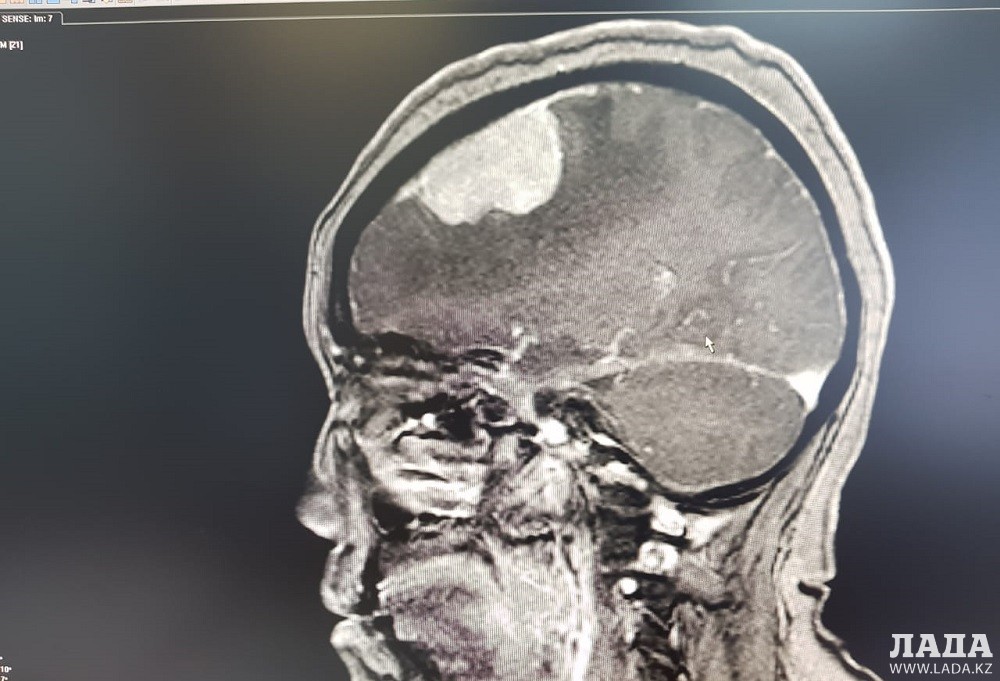

Опухоль мозга диаметром семь сантиметров удалили пенсионерке врачи Мангистау

Дополнительное обследование в аппарате компьютерной томографии (КТ) и магнитно-резонансной томографии (МРТ) показали у пенсионерки наличие отека правого полушария головного мозга.

- Врачи 28 февраля провели операцию по удалению опухоли в правой лобно-теменной области путем костно-пластической трепанации черепа пациентки. Операция прошла успешно, без осложнений, опухоль удалена полностью, - отметили в пресс-службе управления здравоохранения.

Женщину выписали 11 марта. По словам врачей, состояние женщины стабильное, функции головного мозга полностью восстановлены.